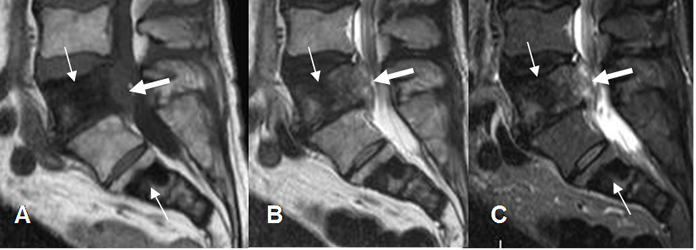

Fig 151. Metástasis blásticas.

A: RM sagital en T1, B: RM sagital en T2 y C: RM sagital en STIR. Lesiones hipointensas en todas las secuencias de tumor de pulmón, en L4 y el sacro, por alto contenido fibroso. En L4 hay masa de tejidos blandos, que ocupa el canal medular. (Flechas gruesas).